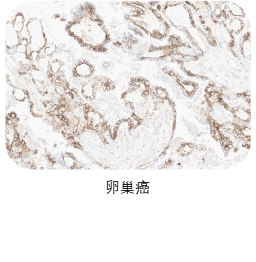

★ 验证充分:三阴性乳腺癌、前列腺癌、胰腺癌、卵巢癌、皮肤癌临床样本充分验证

❷ 适应症癌种染色

选取肿瘤组织样本用于敏感性染色,TROP2一抗染色阳性细胞细胞质和/或细胞膜特异性阳性着色(染色强度≥1),无非特异性着色(染色强度<1),无背景染色(染色强度<1 )。

ACRO IHC实验室目前已建立了成熟的TROP2染色方法与判读体系,适用三阴性乳腺癌、前列腺癌、胰腺癌、卵巢癌、皮肤癌等多个癌种,可快速用于相关肿瘤的临床试验入组筛选与样本检测,部分结果展示如图所示。